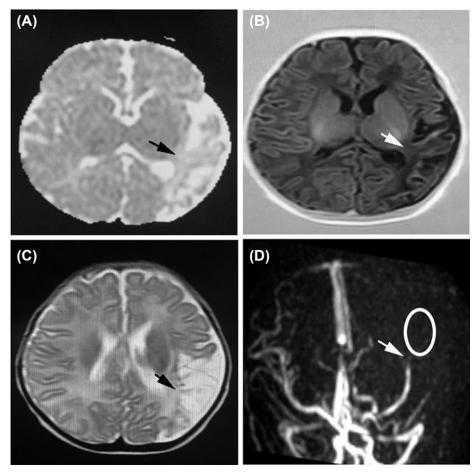

Neonatal arterial ischaemic stroke (NAIS) is caused by focal arterial occlusion and often leads to severe neurological sequelae. Neural deaths after NAIS mainly include necrosis, apoptosis, necroptosis, autophagy, ferroptosis, and pyroptosis. These neural deaths are mainly caused by upstream stimulations, including excitotoxicity, oxidative stress, inflammation, and death receptor pathways. The current clinical approaches to managing NAIS mainly focus on supportive treatments, including seizure control and anticoagulation. In recent years, research on the pathology, early diagnosis, and potential therapeutic targets of NAIS has progressed. In this review, we summarise the latest progress of research on the pathology, diagnosis, treatment, and prognosis of NAIS and highlight newly potential diagnostic and treatment approaches.

新生儿动脉缺血性脑卒中(NAIS)由局灶性动脉闭塞引起,常导致严重的神经后遗症。NAIS 后的神经死亡主要包括坏死、凋亡、坏死性凋亡、自噬、铁死亡和细胞焦亡。这些神经死亡主要由兴奋性毒性、氧化应激、炎症和死亡受体途径等上游刺激引起。目前,NAIS 的临床治疗方法主要集中在支持性治疗上,包括控制癫痫发作和抗凝治疗。近年来,NAIS 的病理学、早期诊断和潜在治疗靶点的研究取得了进展。在这篇综述中,我们总结了 NAIS 的病理学、诊断、治疗和预后研究的最新进展,并强调了新的潜在诊断和治疗方法。